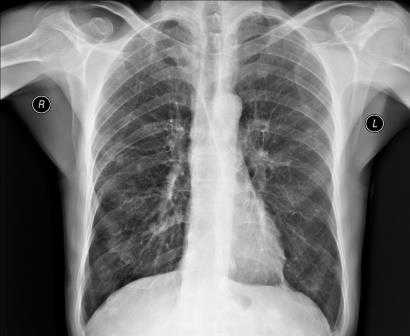

На обзорной рентгенограмме органов грудной клетки (ОГК) в прямой проекции органы средостения формируют тень по форме напоминающую неправильную трапецию. Нижняя половина формируется за счет тени сердца, и небольшой участок за счет нижней полой вены. Верхняя половина за счет теней магистральных кровеносных сосудов (верхняя полая вена, дуга аорты, легочная артерия). По бокам средостения визуализируются корни легких, и легочные поля, снизу купол диафрагмы (Рис. 14).

Для вычисления отклонений от нормы используют кардиоторакальный индекс (КТИ) — отношение поперечного размера сердца к поперечному размеру грудной клетки, измеряемому на уровне правого сердечно-диафрагмального угла (Рис.14).

КТИ = ((Mr+Ml)·100%) / Базальный диаметра грудной клетки. Выделяют 3 степени увеличения КТИ: нормальная величина не превышает 50%; увеличение I степени — 50 — 55%; II степени — 56 — 60%; III степени — более 60%. [5,6]

Рентгенография грудной клетки

Рентгенография грудной клетки – это метод диагностики, позволяющий получить изображение органов грудной полости с помощью облучения рентгеновыми лучами. Различные ткани организма в зависимости от своей плотности по-разному пропускают рентгеновы лучи, а значит, по-разному отображаются на снимке (рентгенограмме).

Рентген грудной клетки дает возможность изучить костные структуры (ребра, грудину, позвоночник), легкие, плевру, бронхи и трахею, сердце и средостение, а также оценить состояние мягких тканей этой области.

Прежде всего, рентген грудной клетки используется для диагностики заболеваний легких.

Что показывает рентген грудной клетки?

Рентген грудной клетки способен выявить:

- присутствие в легких очагов воспаления, в том числе характерных для таких заболеваний как пневмония и туберкулёз;

- наличие опухолевых образований и отеков, которые могут быть следствием сердечной недостаточности;

- наличие патологических скоплений газов и жидкостей;

- скопление жидкости в околосердечной сумке, увеличение размера сердца, аорты и лимфатических узлов;

- инородные предметы в легких, пищеводе и дыхательных путях.